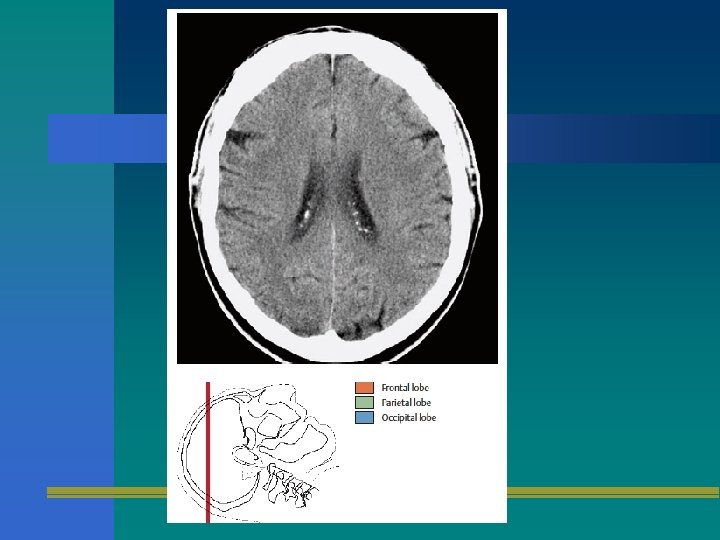

TOMOGRAFIA AXIAL

TAC